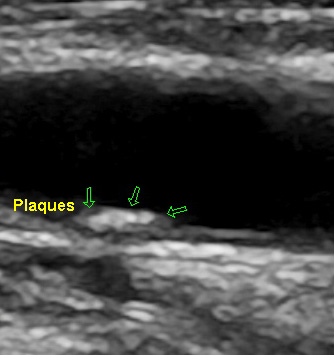

Auf den Bildern sehen Sie einerseits eine glatte Halsschlagader, die Sie schon als solche

erkennen können, weiter eine Halsschlagader mit beginnender Ablagerung (Plaques) und

eine Halsschlagader mit deutlichen Plaquebildungen bis insgesamt zu einer mindestens

70 %igen Verengung. Das erkennt man an dem schwarzen noch offenen Lumen.